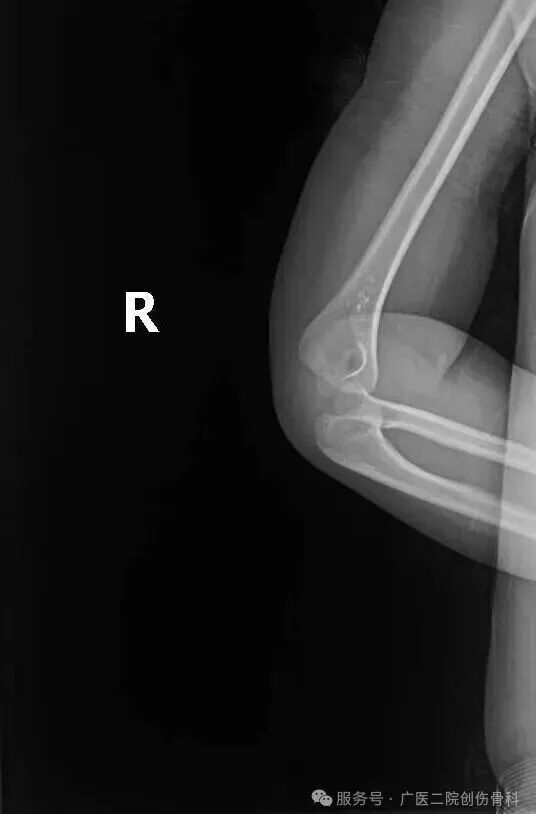

乐乐妈妈带娃来院后,胡海澜通过X光片排除骨折和脱位,结合明确的牵拉史和症状确诊为桡骨小头半脱位。

患儿X光片:肘部未见骨折及脱位征象